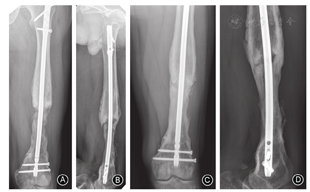

一般选择创伤骨科常规简单切口切开,如有原切口则可沿原切口切开。有窦道者需先梭形切除窦道及周围皮肤,由浅入深切除坏死及失活皮下周围软组织,暴露深部骨组织或内固定材料。去除内固定后,清理螺钉孔和内固定周围肉芽组织。根据术前病灶定位,可以选用电钻钻孔槽形或椭圆形开窗,或者节段切除病灶骨质,使用刮匙清理髓腔内死骨与肉芽组织,软杆扩髓器进一步清理髓腔,直至骨折端见"点状出血征"。根据需要术中留取标本做微生物学或病理学检查,并以双氧水及碘伏消毒,同时使用脉冲冲洗工具清洗术区。然后使用骨刀或磨钻等工具继续沿骨质表面去除边界骨质5 mm,并按"地毯式"进一步清理周围失活的软组织(表面苍白),再次消毒及使用脉冲冲洗伤口。术区重新消毒后,更换无菌单及手术器械,手术人员更换手套和手术衣。骨折端使用外固定架或抗生素骨水泥被覆钢板固定。通常在40 g庆大霉素骨水泥粉剂中加入5 g万古霉素,混合均匀后加入液态单体,面团期以2 cm3体积大小逐个放入骨缺损区,骨折端平滑包裹超过2 cm[13],抗生素骨水泥完全包裹内固定物(图2)。待骨水泥发热塑形后,使用冰生理盐水浸泡或冲洗降温。留置引流管,缝合术区。

膜诱导重建可加速骨愈合,患者术后早期可完全负重[48]。虽然不同文献报道膜诱导重建术后骨愈合时间不一,但影像学检查示骨愈合时间一般为4~8个月[17,49]。Yeganeh等[50]研究发现,年龄、骨缺损长度和感染时间均对骨缺损修复无影响,但可能与植骨材料中自体骨的含量过低、骨折固定方式、低毒力细菌感染等相关。当膜诱导重建过程中发生骨延迟愈合后,不要急于外科干预,可指导患者行负重训练,其中一部分患者可在骨移植术后1~2年缓慢愈合(图7)。当内固定已失效或等待时间超过2年时,可考虑再次手术干预。